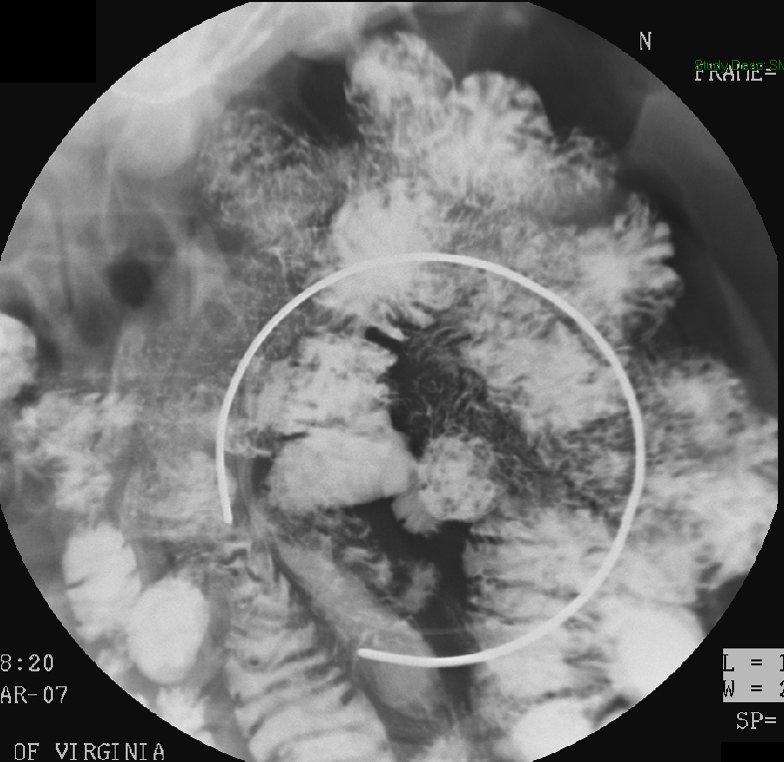

- Ileoanal J Pouch

- The iloeanal J pouch is created when patients have a total proctocolectomy.

- During this exam, you will focus on the bowel in the pelvis.

- When reviewing the preliminary scout film, you should see multiple surgical chain sutures in the pelvis

(key image 31)

(key image 32).

- After the enema tip has been placed but before contrast material has been administered, obtain a fluoroscopic spot film of the rectum with the patient in the left lateral position

(key image 33).

- As you instill contrast material into the J pouch, obtain images of the pouch and ileoanal anastomosis fully distended with contrast material in each of the following four (4) positions:

- left lateral

(key image 34)

- left posterior oblique

(key image 35)

- supine (AP)

(key image 36)

- right posterior oblique

(key image 37).

- Contrast material may be seen filling the ostomy bag (if present) before all images have been obtained. If this happens, proceed to take the needed images, adjusting the postion of the ostomy bag if needed.